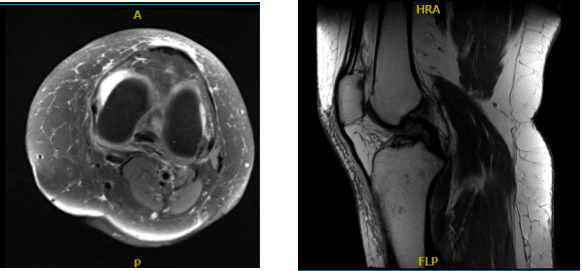

We performed an MRI, which revealed a high-grade partial ACL injury. Take into account that the patient was young, sick, and we talked about our alternatives. The knee also had very little arthritis. Treatment alternatives were explored, including well-known surgical management.

MRI-3T Left Knee non-contrast